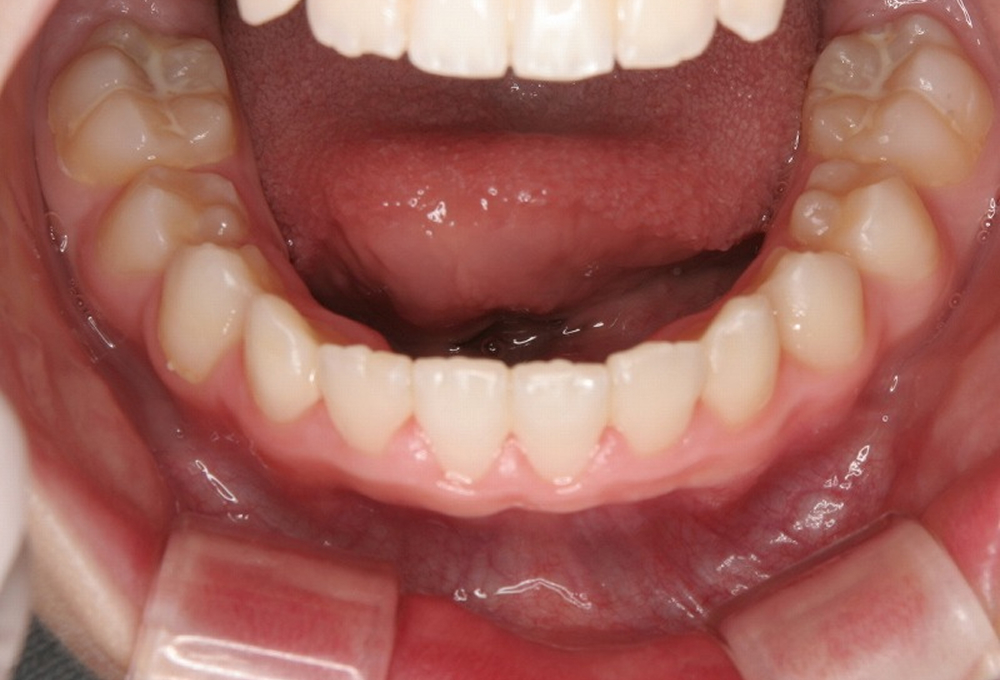

③術前 下顎 叢生